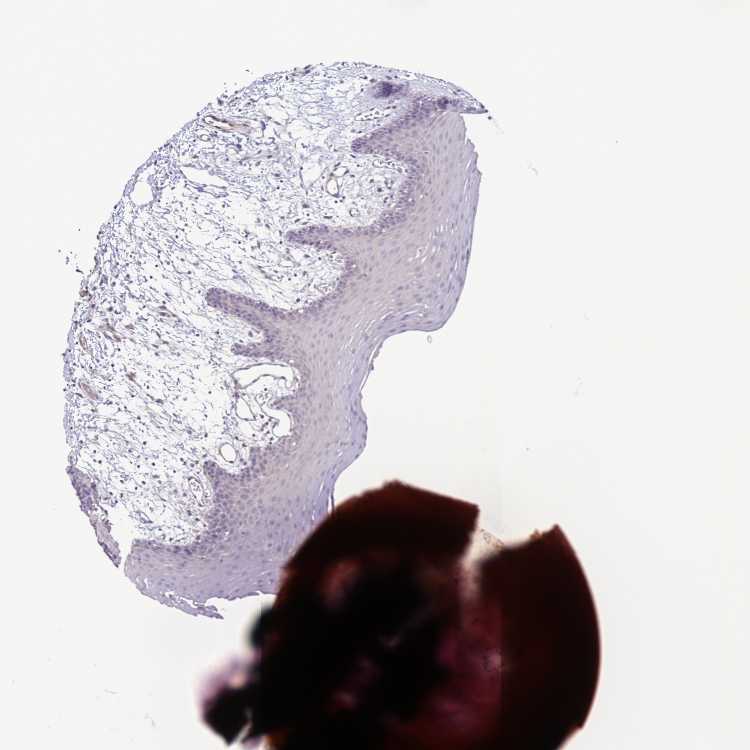

ORAL MUCOSA - Antibody stainingi

Antibody staining in the annotated cell types in the current human tissue is reported as not detected, low, medium, or high, based on conventional immunohistochemistry profiling in selected tissues. This score is based on the combination of the staining intensity and fraction of stained cells.

Each image is clickable and will lead to virtual microscopy that enables deeper exploration of all samples and also displays staining intensity scores, fraction scores and subcellular localization as well as patient and tissue information for each sample.

Antibody HPA045098

Squamous epithelial cells Not detected